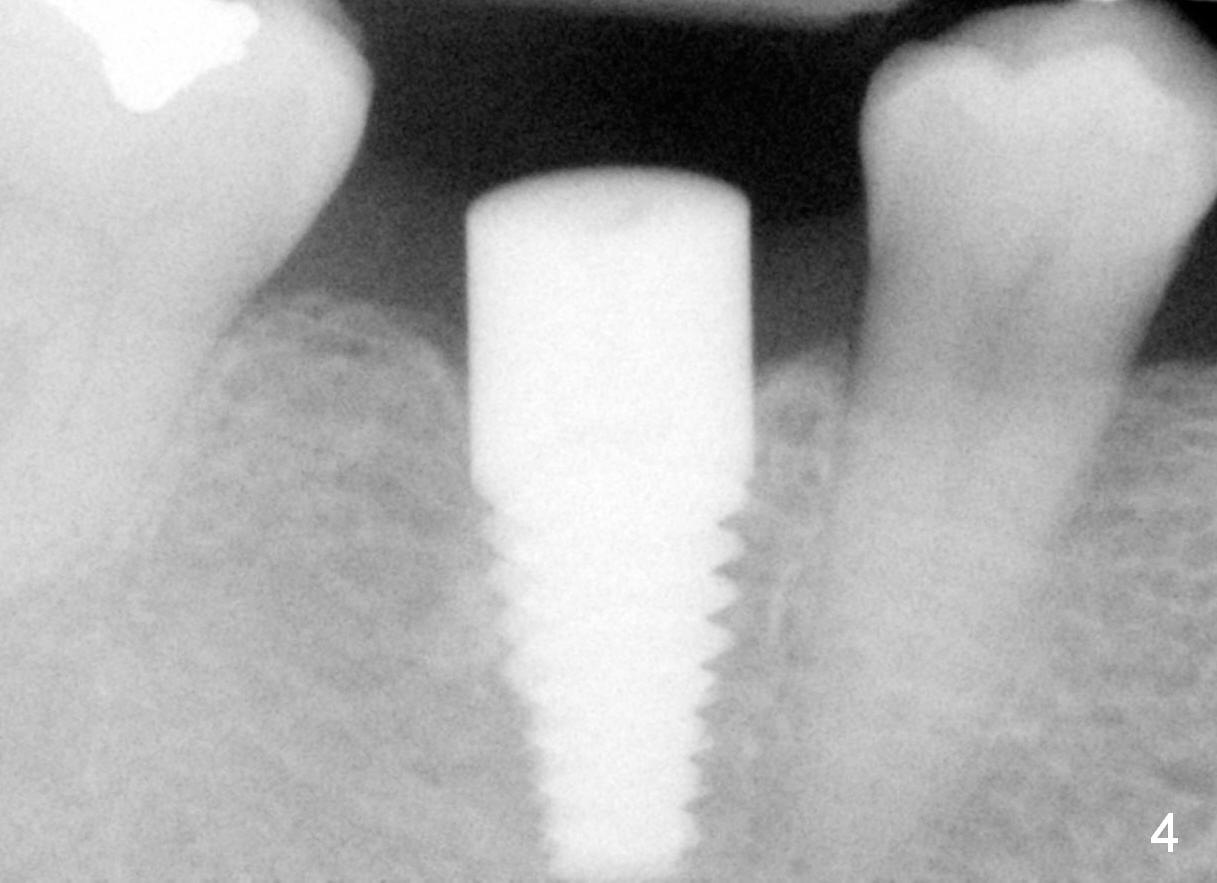

Six years ago, a 38-year-old patient presented to our office for new patient exam. She was scared of dentistry, but 3 of the third molars needed extraction. When the surgery was done painlessly, it was not too hard to persuade the patient to accept implant placement at the site of #30 (Fig.1; N: Inferior Alveolar Nerve). It was the 1st case when a 2nd implant system was adopted in the office. The implant is 3 mm shorter than the design (Fig.2). An incision was made for visibility (Fig.3). There is no bone loss 3.5 months postop (Fig.4). The crown is cemented 5 months postop (Fig.5); there is attached gingiva buccal to the implant. What surprised us the most is that she turns out to be one of the most faithful patients in our office. She never misses 6-month recall.